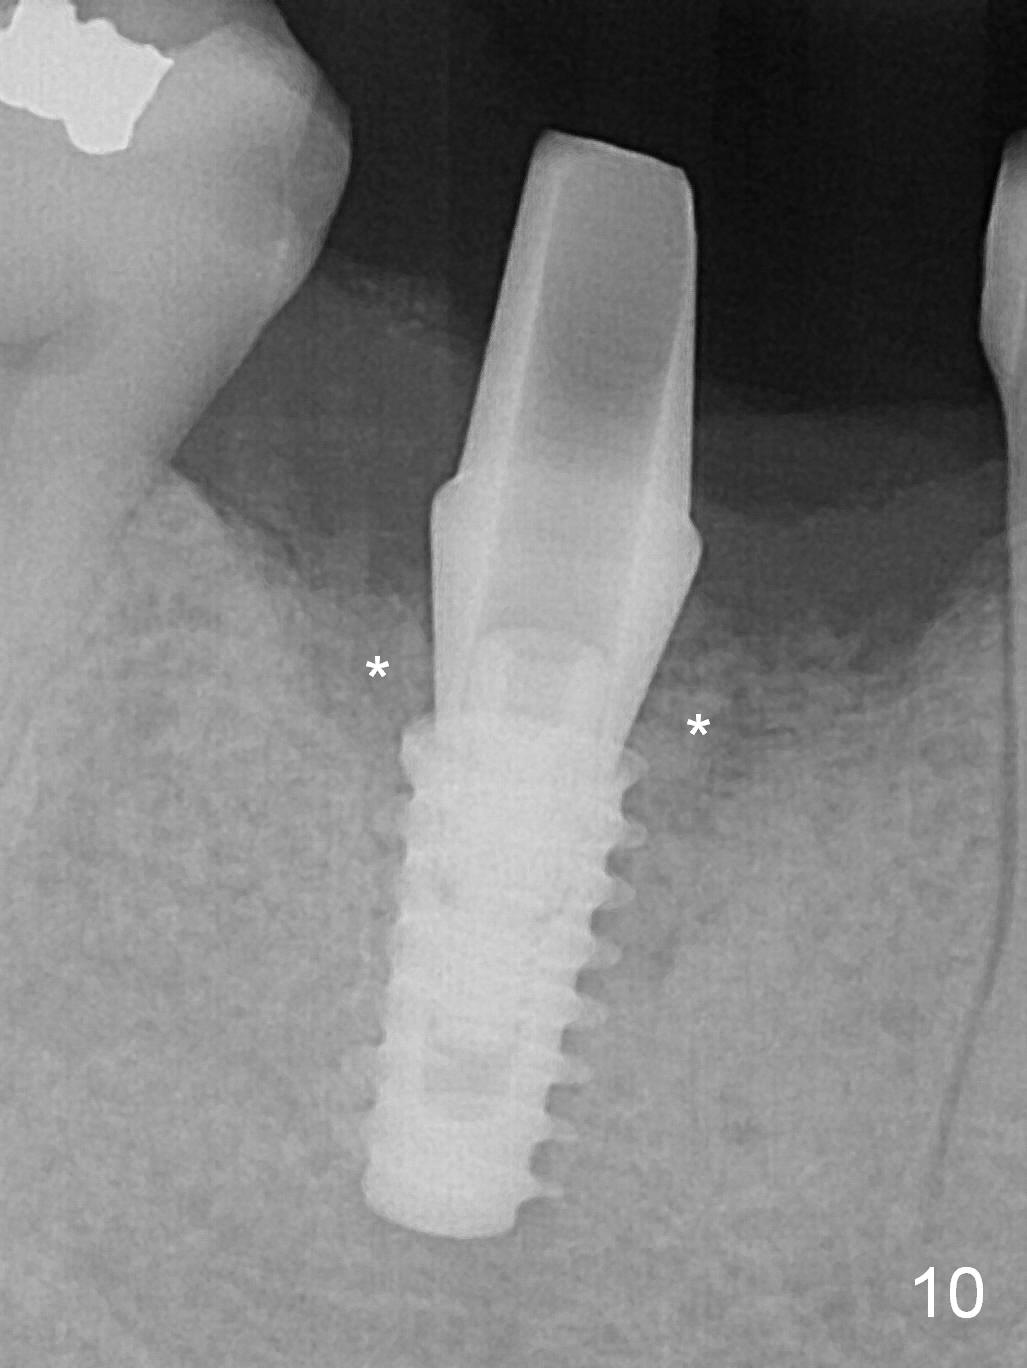

A 49-year-old man develops acute abscess of the lower right quadrant (Fig.3-5) secondary to periimplantitis at #30 (Fig.1,2,6). The latter is probably due to buccal placement (Fig.6 (*: buccal plate)). After removal of the infected implant, an osteotomy is established as lingual as possible using single drill modality (Fig.7 (4.3 mm Magic Drill after 1.6 mm pilot drill and Marking Bur, then Final Drill). With the single drill, the osteotomy does not shift buccally in spite of the lower buccal plate. A 5x9 mm IBS implant is placed lingually as planned (Fig.8 (>40 Ncm)), followed by an angled abutment (5 mm x 15° (4 mm)) (Fig.9 A). The buccal gap is filled with autogenous bone, allograft (.5-1.5 mm) and Osteogen (Fig.10 *), covered by resorbable and non-resorbable membranes. After suturing, periodontal dressing is applied.